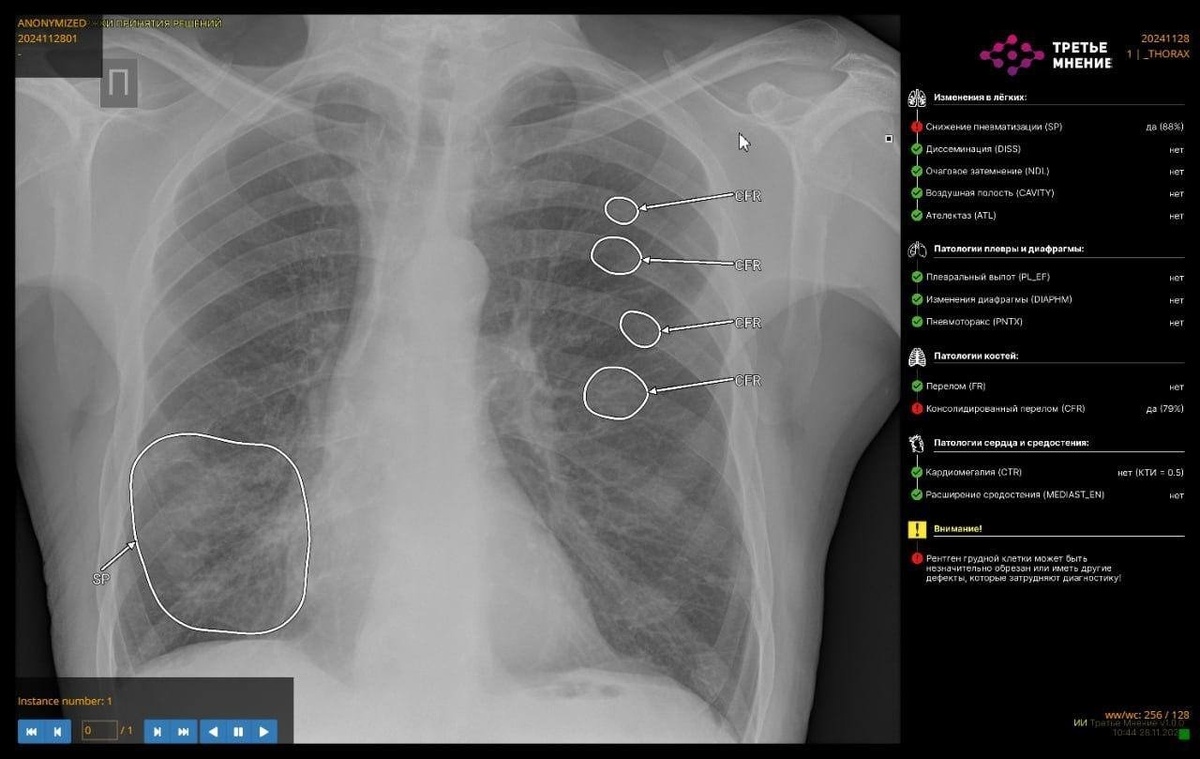

В 50 больницах Башкирии используют ИИ для получения второго мнения

Лучевые диагносты 50 больниц используют искусственный интеллект для интерпретации исследований и получения второго мнения в Башкирии. Как сообщил в своих соцсетях министр здравоохранения РБ Айрат Рахматуллин, развитие комплексных сервисов — одно из ключевых направлений работы ведомства при применении технологий искусственного интеллекта. Например, на КТ органов грудной клетки комплексный сервис способен определять до 14 видов патологий. В будущем планируется добавление сервисов по аналитике бронхоэктазов, фиброзов и эмфиземы легких.

Новые направления, которые научились выявлять ИИ-сервисы — это пневмоторакс, изменения подмышечных лимфоузлов на КТ органов грудной клетки, переломы ребер, инфильтрация легочной ткани (пневмония), плеврит (скопление жидкости в плевральной полости), объемное образование надпочечников, костная патология позвоночника.

«ИИ-сервисы уже компетентны в анализе изменения лимфоузлов: сервис подсвечивает врачам патологическую зону, которую в дальнейшем врач-клиницист сопоставляет с результатами исследования и симптомами. Таким образом, ИИ способен обнаружить признаки заболеваний, даже если они не были целью обследования, что позволяет пациентам раньше начать лечение для скорейшего выздоровления», — рассказал Айрат Рахматуллин.